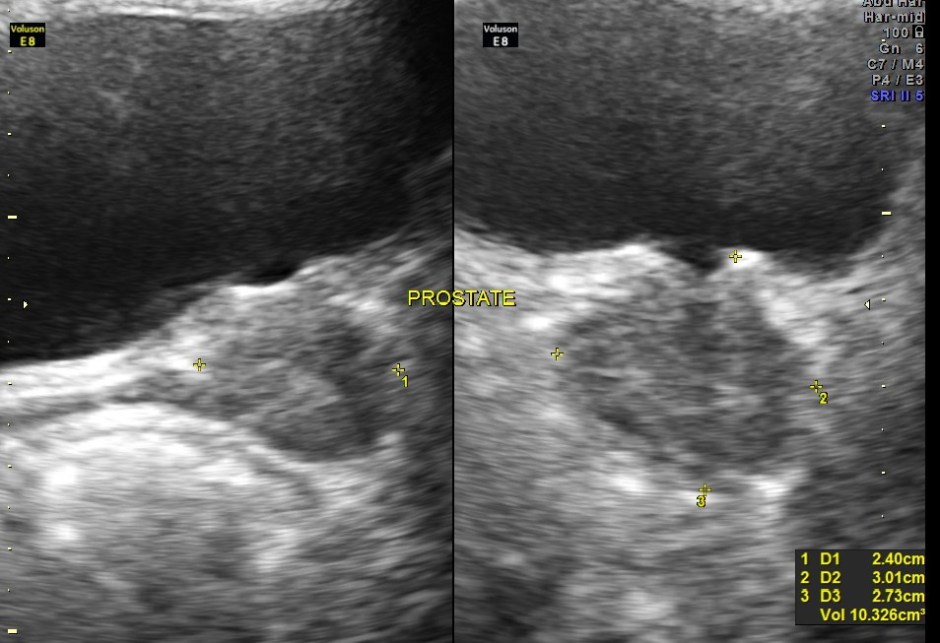

An ultrasound abdomen was done as part of evaluation of anemia.